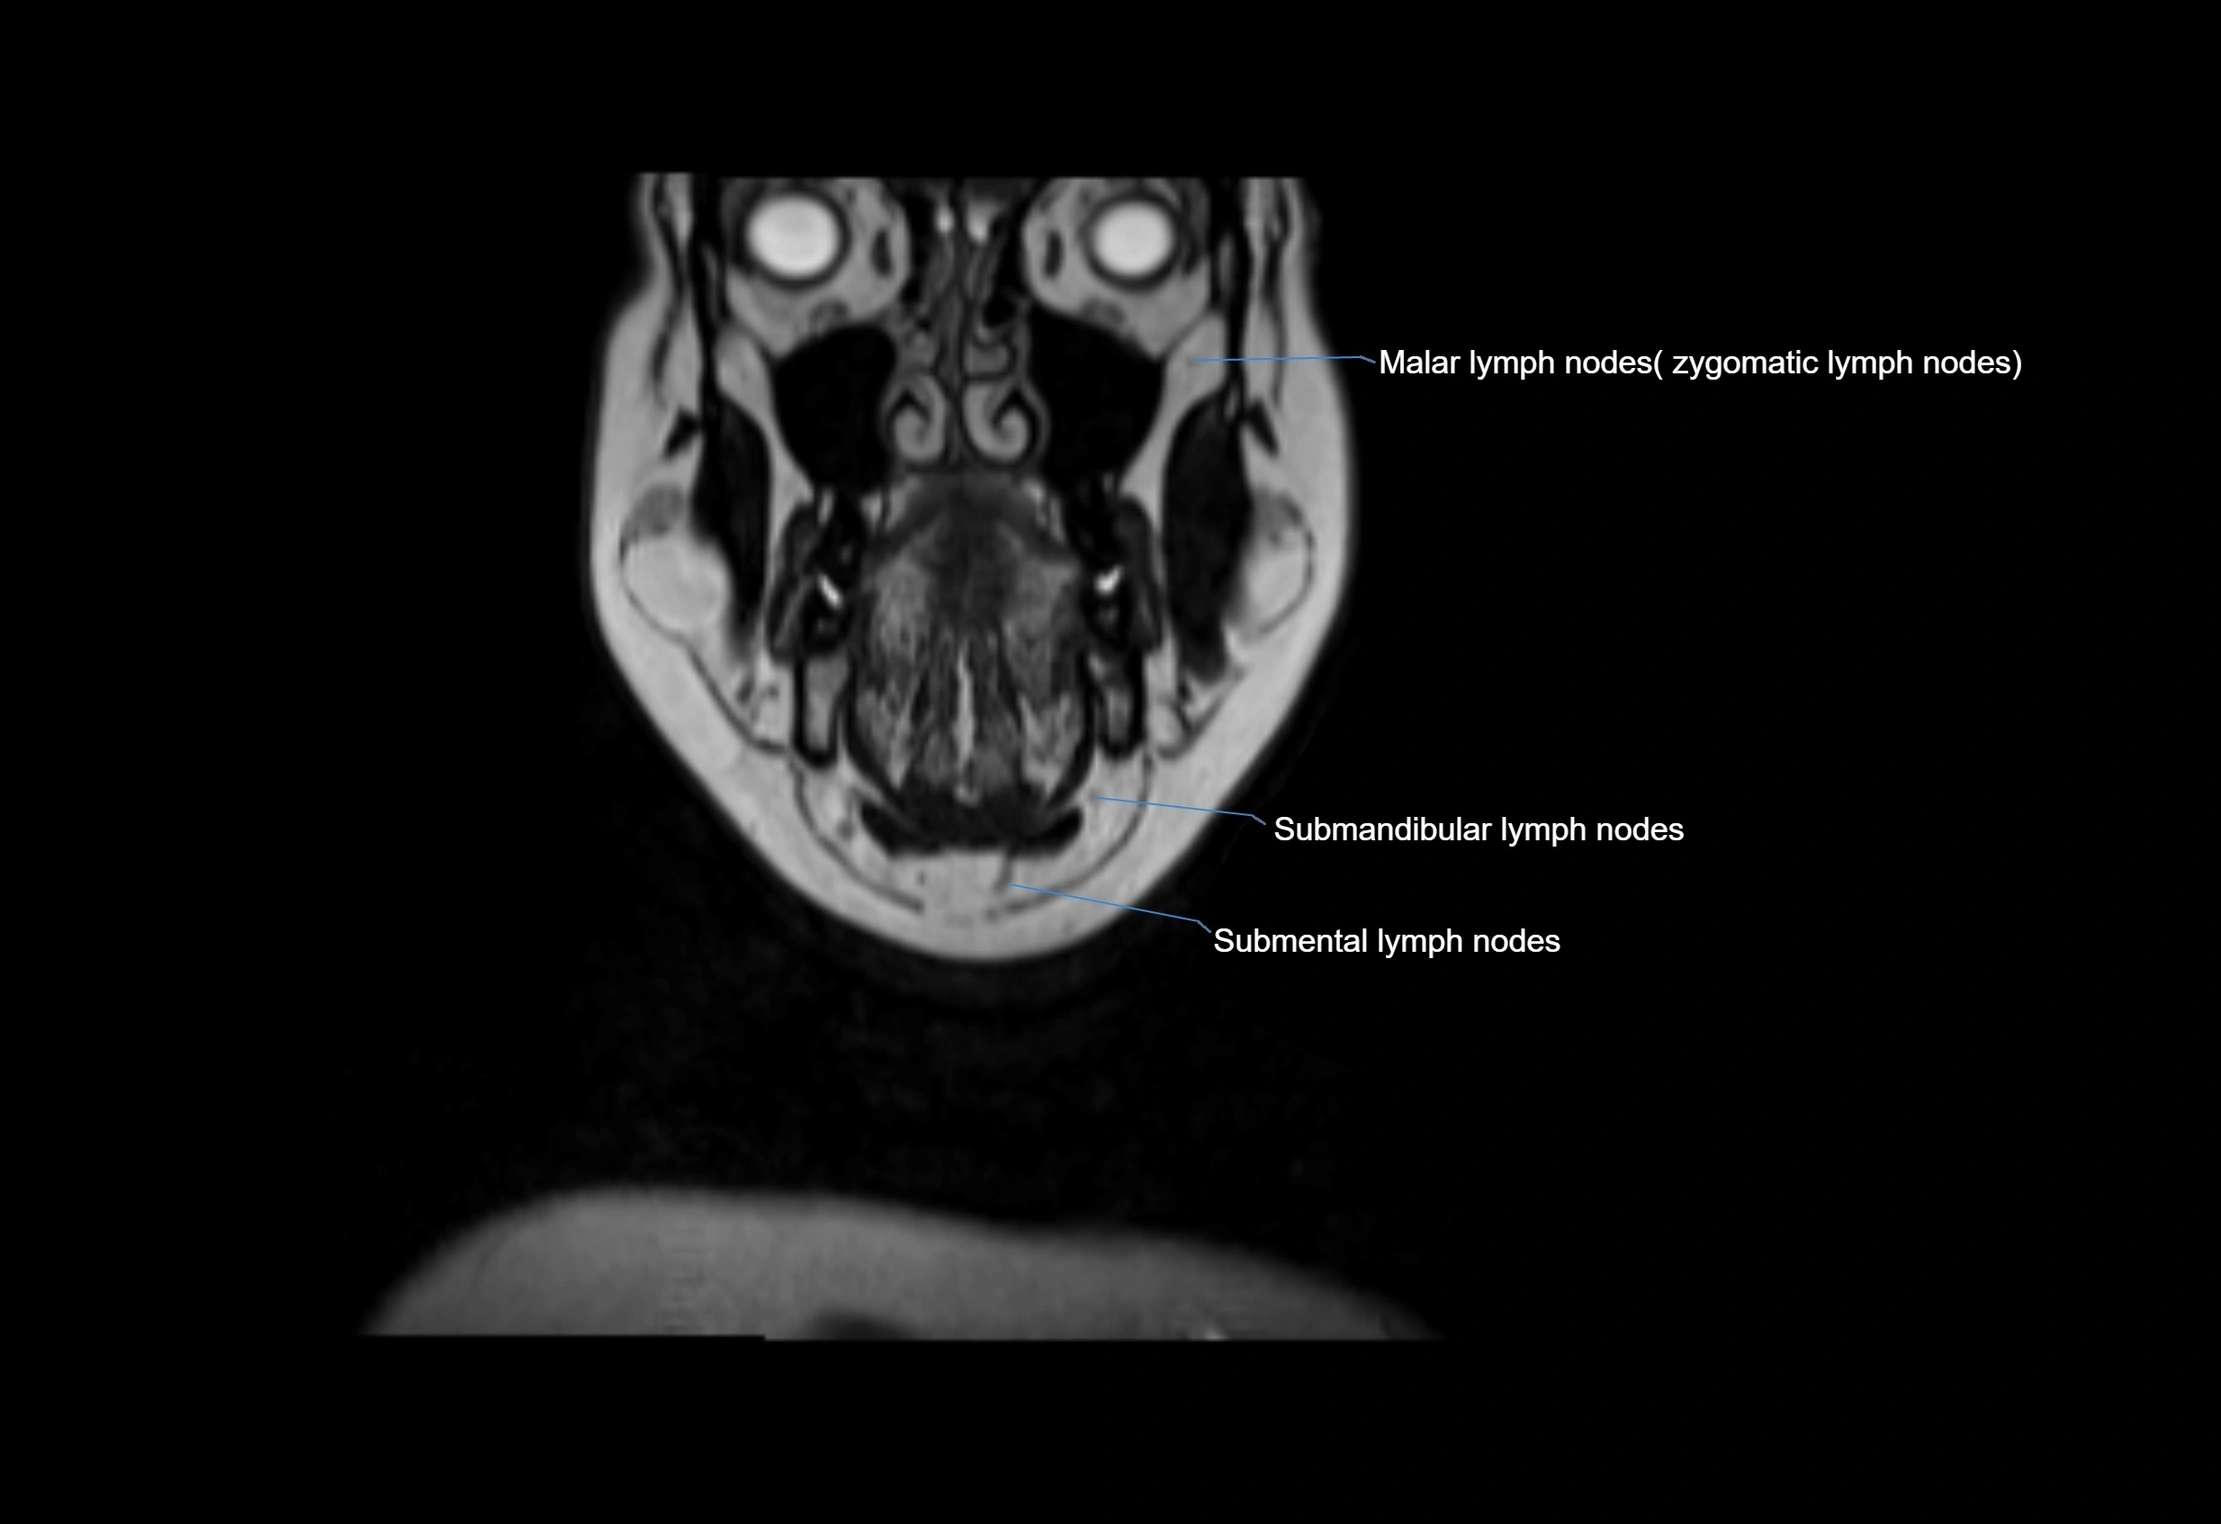

Location

• Found along primary lymph node chains, including preauricular, submandibular, parotid, and occipital regions

• Embedded in subcutaneous fat or superficial fascia, often lateral or posterior to primary nodes

MRI Appearance

T1-weighted images:

• Normal accessory nodes appear as small, oval hypointense to intermediate signal structures within subcutaneous fat

• Surrounded by hyperintense fat, enhancing contrast for visualization

• Pathological nodes may appear enlarged or rounded, sometimes with cortical thickening

T2-weighted images:

• Nodes show intermediate signal, with surrounding fat bright

• Useful for detecting edema, inflammation, or infiltration

• Fatty hilum may appear slightly hyperintense relative to cortex

MRI images